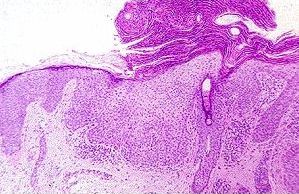

Actinic keratosis with all the typical features:

hyperkeratosis, parakeratosis, dysplasia and solar keratosis.

Histologically, seborrheic keratosis has the following features:

• the base of the seborrheic keratosis is flat and level with the base of the adjacent normal epidermis (ie. an exophytic appearance if the adjacent normal epidermis is included)

• acanthosis (thickening of the epidermal layer; in seborrheic keratosis this results from basaloid cell proliferation. Dysplasia is absent)

• hyperkeratosis (excess keratin)

• epidermal cysts filled with keratin (horn cyst) are common, some of these cysts resulted from infoldings of the epidermis (pseudohorn cysts).

• hyperpigmentation of the basaloid cells from melanin phagocytosis

• solar elastosis

A seborrheic keratosis with an exophytic appearance. The base of the lesion is

level (arrowed) with the normal epidermis (N) on the left. Two pseudohorn cysts

(PH) are seen here which are formed from infoldings of the epidermis.